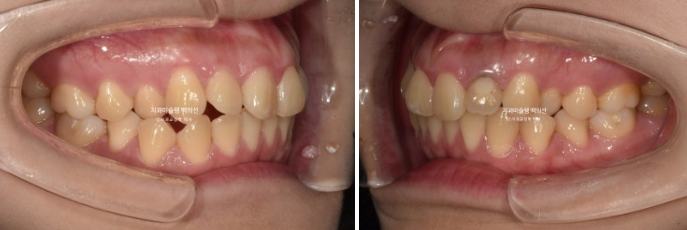

23년 12월 교정치료를 위해 멀리 지방에서 오신 환자분입니다.

환자가 고치고 싶은 것은 배열, 교합, 거미스마일(잇몸미소) 마지막은 비대칭 입니다.

교합은 거꾸로 물리는 어금니 반대교합도 있고, 뜨는 부분도 있고 앞니 하나는 신경치료 후 변색이 되어 있습니다.

작은어금니가 입천장으로 들어가 있어 반대교합 상태였습니다.